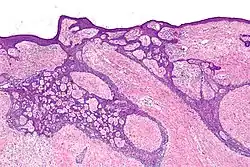

High-magnification micrograph of basal-cell carcinoma

Basal-cell carcinoma cells resemble epidermal basal cells and are usually well differentiated.[27]

In uncertain cases, immunohistochemistry using BerEP4 can be used, having a high sensitivity and specificity in detecting only BCC cells.[28]